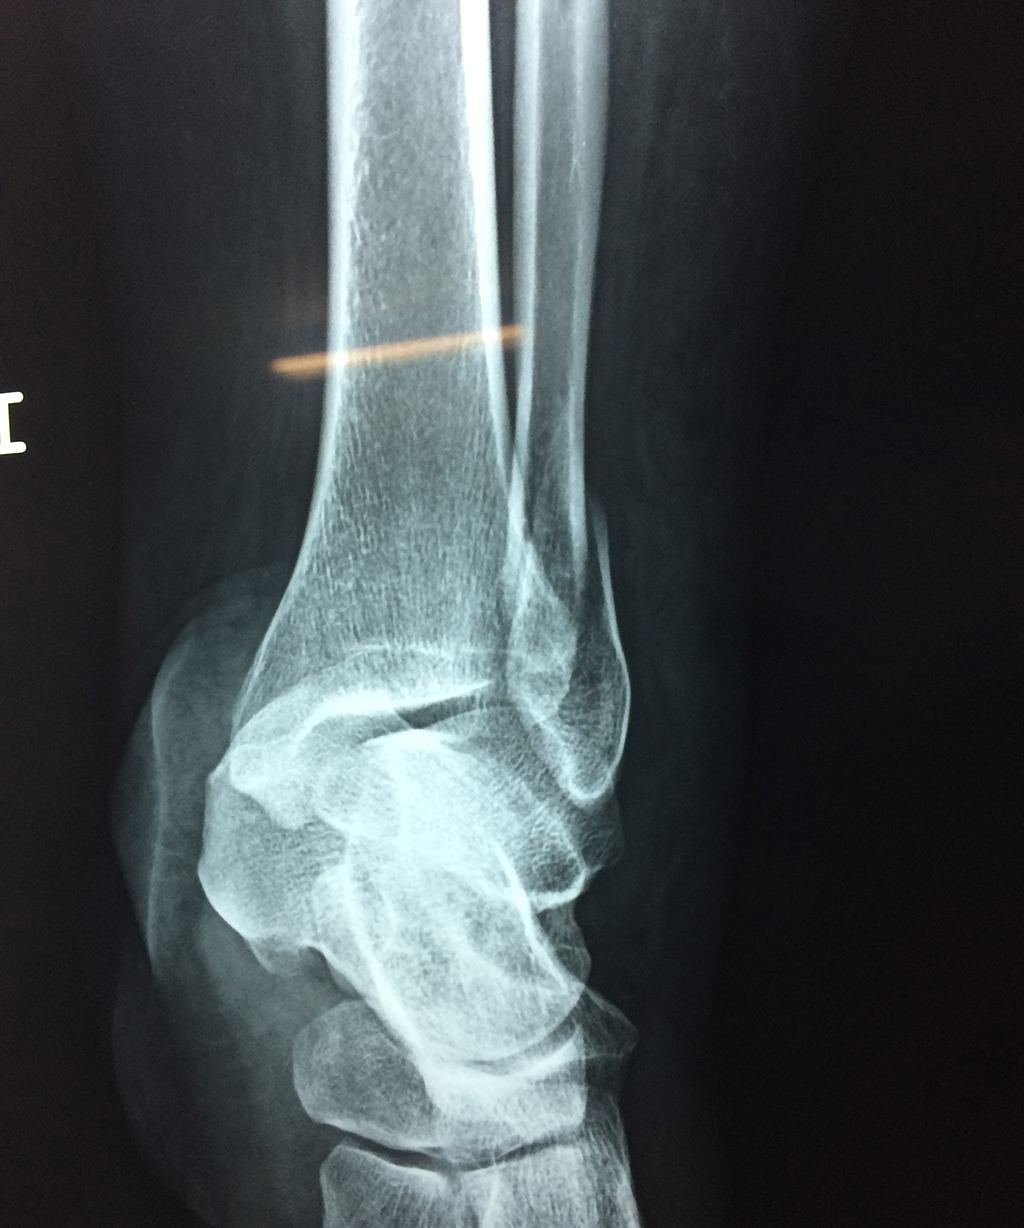

- Los extremos de los huesos están desalineados entre sí (desplazados).

- La fractura se extiende hasta la articulación del tobillo (fractura intra-articular).

Cuando se necesita cirugía, es probable que esta implique el uso de clavijas de metal, tornillos o placas para sostener los huesos en su lugar mientras la fractura se consolida. Los elementos de soporte pueden ser temporales o permanentes.